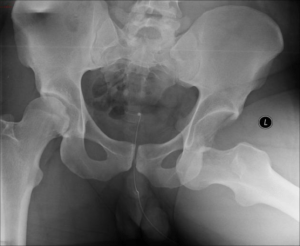

Illustration 1– An x-ray of a severely dislocated hip

MVA related hip dislocations are usually caused by the knee being slammed into the dashboard, which causes a displacement of the hip. Individuals who experience a dislocation will know it immediately as they will feel their hip pop “out of place”. It’s likely that walking or even standing will be very difficult. Because of this, emergency treatment is necessary. If there’s an associated fracture, surgical intervention might be necessary.